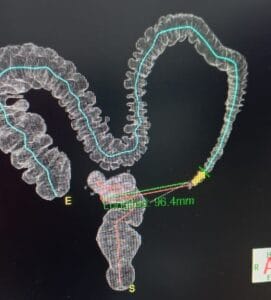

COLONOSCOPIA VIRTUAL

La colonoscopia virtual, también conocida como colonografía por tomografía computarizada (TC) o colonografía por resonancia magnética (RM), es una técnica...